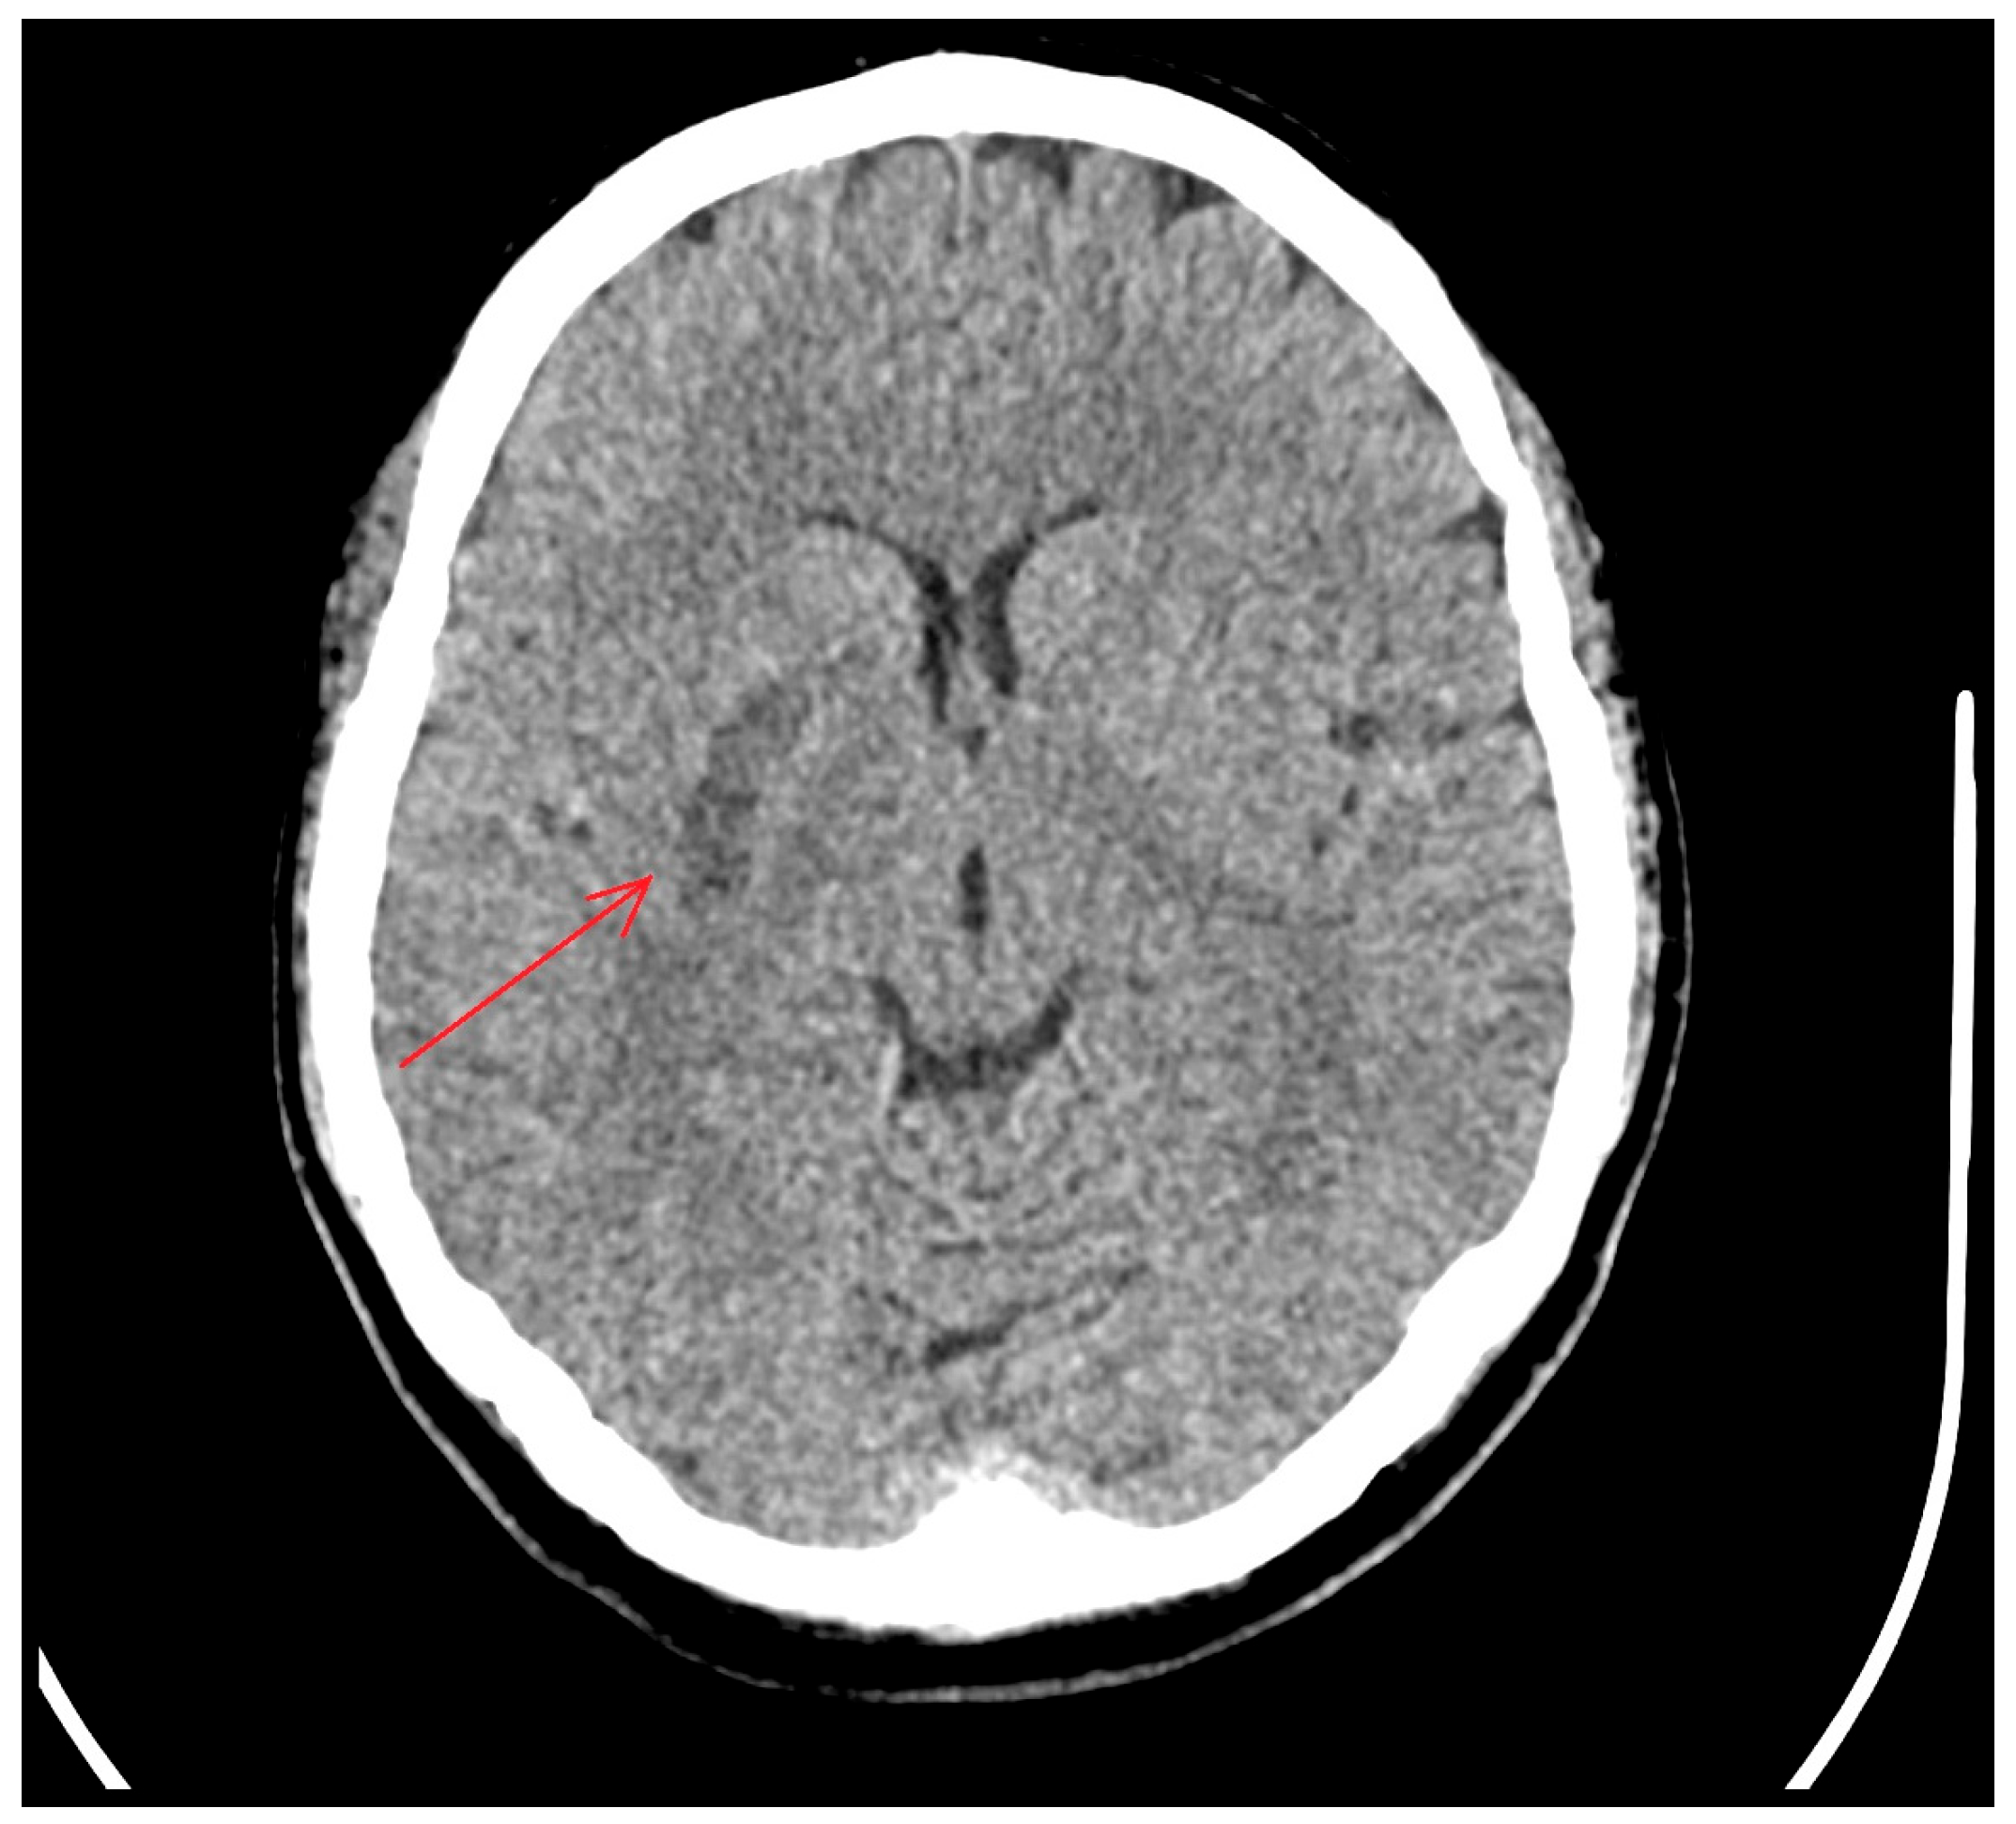

2. Case Presentation

3. Diagnostic Assessment